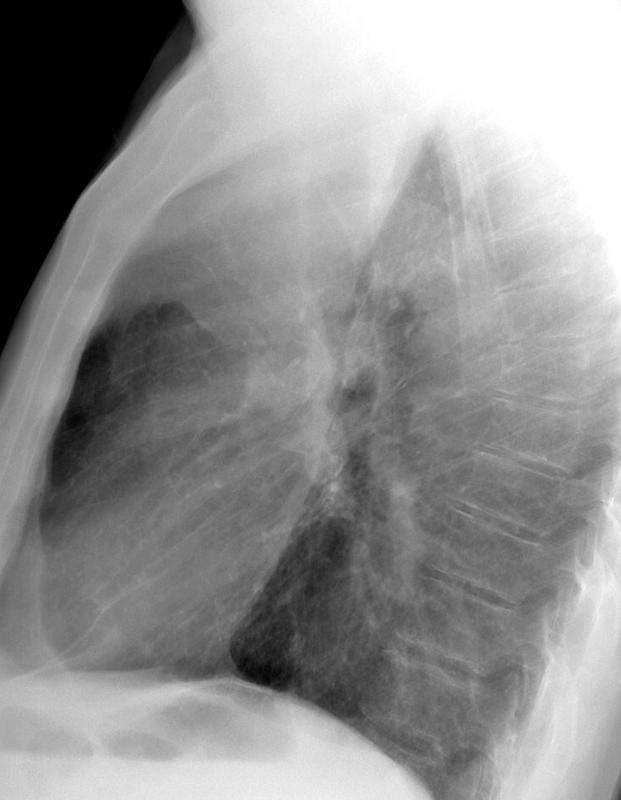

Lobar Collapse

RUL Collapse

RUL Collapse Case 9 Lat